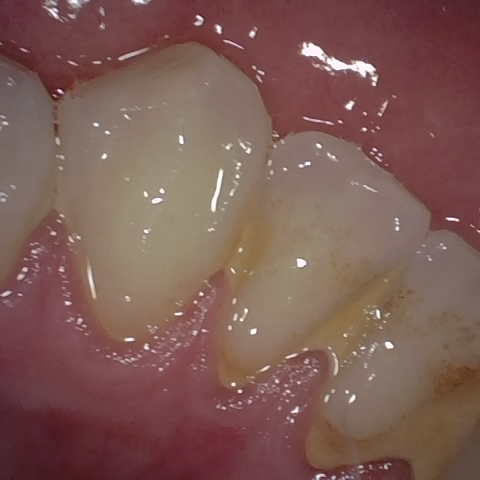

Image 290 / 1527

NHD39455

Annotated as "Good"

Original Image Rendering Image